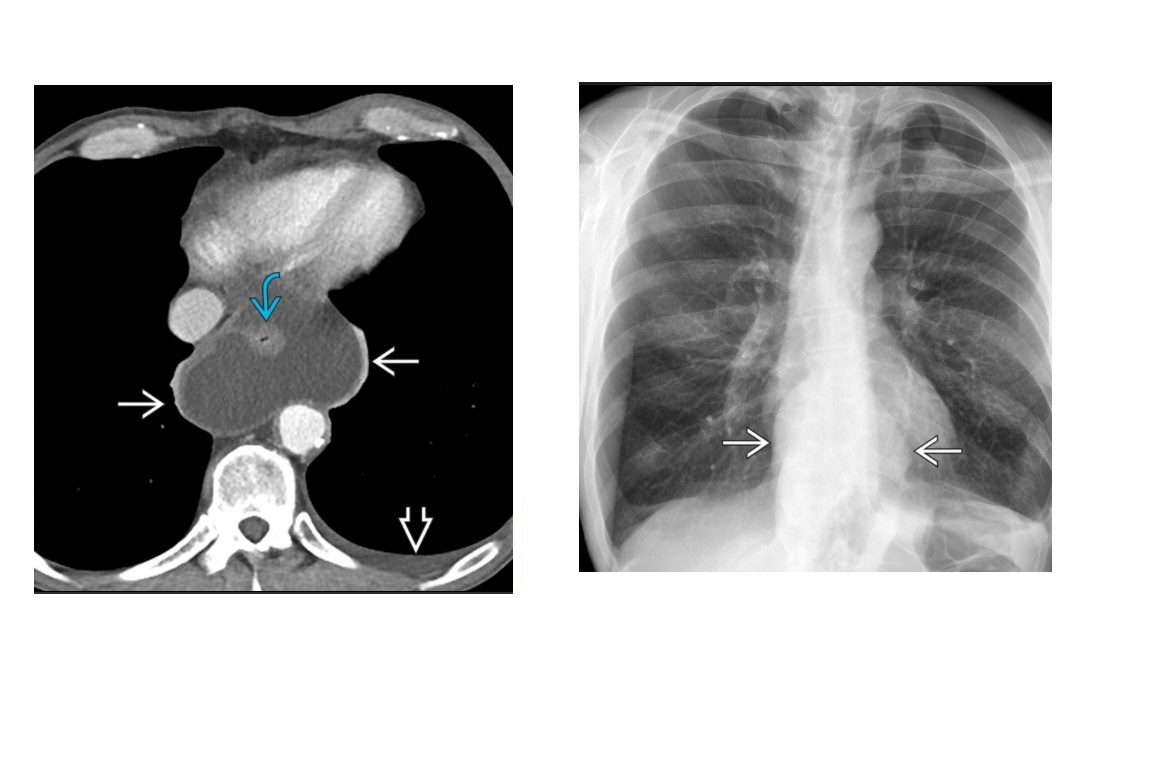

Budd-Chiara vs Veno-occlusive vs passive congestion?

Budd-chiara Acute - Ascites, pain, narrowed and thrombosed IVC and hepatic veins - 'Flip - flop' - early arterial central caudate lobe and central and relatively less enhancement peripherally. on portal venous phase this is the opposite. -** Reversed flow portal vein (hepatofugal)** Chronic - Large regenerative nodules on dysmorphic liver - enhancing, hyperdense, central scar - caudate lobe hypertrophy and peripheral atrophy - Total obliteration of IVC/hepatic - Collateral veins Causes Budd-Chairi - Thrombosis of hepatic veins = OCP, thrombocytosis, pregnancy - Non-thrombotic causes = right atrial myoxma, mechanical compression by tumour, constrictive pericarditis Veno-occlusive - Occlusion of small hepatic venules - **Jamaican bush tea and Stem cell transplant** - Main IVC and hepatic veins are patent, but portal waveforms abnormal Passive congestion - CCF or constrictive pericarditis - enlarged hepatic veins and IVC - Increased portal vein pulsatility